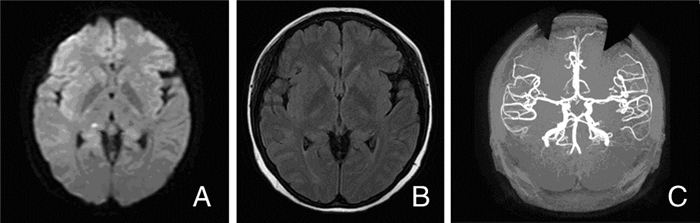

入院后第2天患者间断发热,体温波动于36.5℃~38℃,可自行热退,降钙素原0.07 ng/mL,血常规:WBC:2.67×109/L,Hb:77 g/L,PLT:108×109/L。第4天体温达38.9℃,患者精神萎靡,间断发作一过性意识模糊,呼之不应,头痛,恶心,呕吐并出现复视。查体:左眼外展及下视受限,余查体同前。复查血常规:WBC:2.09×109/L,Hb:74 g/L,PLT:89×109/L。降钙素原0.1 ng/mL。凝血功能:凝血酶原时间16.1 s(正常值9.4~12.5 s),凝血酶原活动度57%(正常值80%~160%)。铁蛋白975 ng/mL。胆囊超声:胆囊壁增厚、毛糙,胆囊多发结石。患者发热,有颅内压增高表现,考虑中枢感染,因凝血功能异常,血小板进行性下降,出血风险高,暂缓腰穿。外周血三系血细胞进行性下降,铁蛋白增高,行骨穿:可见噬血细胞,结合腹部超声及Murphy征阳性,补充诊断:①噬血细胞综合征;②胆囊炎。予美罗培南及甲泼尼龙治疗10 d后患者体温正常,右上腹压痛消失,Murphy征阴性,复查血常规:WBC:3.14×109/L,Hb:82 g/L,PLT:107×109/L。骨穿未见明显异常。停用美罗培南,甲泼尼龙逐渐减量,患者精神好转,间断一过性意识丧失,发作时伴右上肢强直震颤,双眼凝视,约10 S后可自行缓解。头痛,为左侧额颞部及左眼眶周疼痛,复视,恶心、呕吐,此时患者凝血功能大致恢复正常,不除外中枢感染,行腰椎穿刺术。脑脊液:压力>330 mmHg,氯109 mmol/L,总蛋白162.07 mg/dL,糖0.85 mg/dL,墨汁染色可见隐球菌,抗酸染色阴性。复查头颅MRI+DWI+SWI+MRA:左侧颞叶、左侧大脑脚多发斑片状及斑点状DWI高、稍高信号影。右侧丘脑斑点状短T1长T2信号,FLAIR高信号影,边界清。双侧大脑半球多发条状FLAIR高信号,SWI、MRA未见异常(图 2)。补充诊断:新型隐球菌性脑膜炎。予氟康唑抗新型隐球菌治疗,甲泼尼龙逐渐减量至12 mg/d,白细胞及血小板计数未见下降,血红蛋白波动于82~95 g/L。氟康唑应用3周后患者未再发作一过性意识丧失,头痛较前好转,复查腰穿,脑脊液墨汁染色仍可见隐球菌,抗酸染色阴性,压力240 mmHg,氯136 mmol/L,总蛋白66.25 mg/dL,糖19.72 mg/dL。后患者继发泌尿系感染,再次发热,出现昏睡,病情恶化,由于经济原因,患者家属放弃治疗出院。其他辅助检查:抗中性粒细胞胞浆抗体阴性,抗链球菌溶血素O阴性,类风湿因子阴性,抗核抗体谱筛查未见异常。抗心磷脂抗体:阴性。血同型半胱氨酸:4.2 μmol/L。梅毒+HIV:阴性。常规心电图及超声心动图未见异常。甲状腺功能及抗甲状腺抗体未见异常。

| 图 2 患者2018-01-31的MRI图像 注:A:双侧大脑半球多发条状FLAIR高信号,右侧丘脑斑点状FLAIR高信号影;B:左侧颞叶斑片状DWI高信号影;C:右侧丘脑及两侧基底节区多发斑点状T2高信号影 |